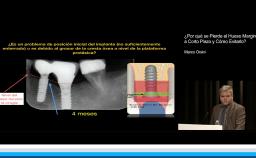

En esta conferencia, el Dr. Rodrigo presta especial atención a todos los aspectos de riesgo englobados en el manejo del paciente periodontal en tratamiento con implantes, efectuando una exhaustiva revisión de la evidencia existente y con abundante iconografía. Se revisan factores de riesgo tales como el biológico, incluyendo tanto la genética como la microbiología pasando por el diseño personalizado de la prótesis, el riesgo estético y las limitaciones de nuestro tratamiento respecto a las expectativas de los pacientes y finalmente el riesgo quirúrgico o como simplificar nuestros procedimientos en estos pacientes de alto riesgo, mediante el empleo de implantes cortos, estrechos, angulados e inmediatos.